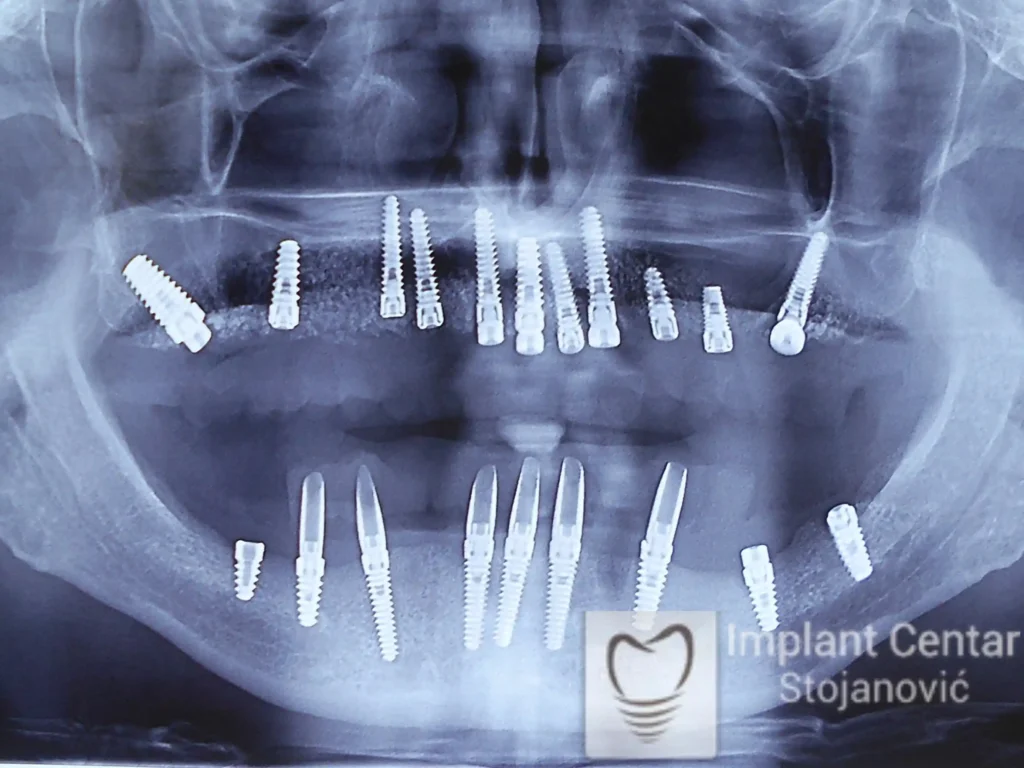

Pacijent sa rascepom usne, nepca i alveolarnog grebena uspešno je rehabilitovan fiksnim protetskim radom na implantatima. Pre dolaska u našu ordinaciju, pacijent je u gornjoj vilici nosio totalnu protezu preko preostalih zuba, dok je u donjoj vilici bio zbrinut parcijalnom mobilnom protezom. Tokom višegodišnje potrage za adekvatnim rešenjem, pacijent nije uspeo da pronađe zadovoljavajuću terapijsku opciju ni u zemlji ni u inostranstvu.

Nakon detaljnog kliničkog pregleda i analize radioloških snimaka, izrađen je sveobuhvatan plan terapije sa ciljem uklanjanja mobilnih proteza i postizanja maksimalne funkcionalne i estetske rehabilitacije. Zbog loše biološke vrednosti preostalih zuba, doneta je odluka o njihovom vađenju i ugradnji dentalnih implantata.

Poseban terapijski izazov predstavljalo je premošćavanje defekta nastalog usled rascepa, kao i ograničena količina raspoložive kosti u gornjoj vilici. Primenom većeg broja implantata i odgovarajućih procedura nadoknade kosti, postignuta je stabilna osnova za fiksni protetski rad.

Tokom perioda oseointegracije, pacijent je bio zbrinut fiksnim privremenim krunicama, čime je već pet dana nakon intervencije obezbeđena potpuna funkcionalna i estetska rehabilitacija. Nakon završetka perioda integracije implantata, izrađeni su definitivni cirkonijum-keramički mostovi na implantatima.